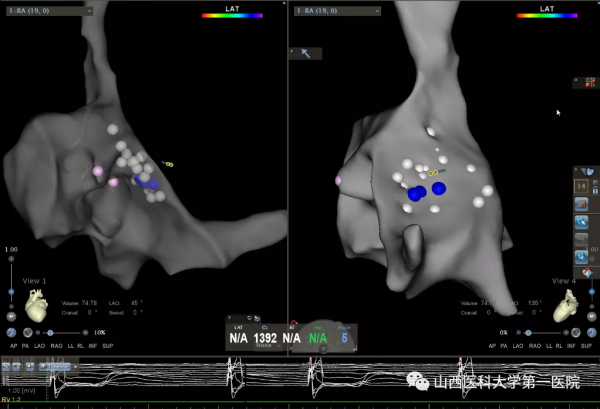

9月10日上午,心血管內科起搏電生理團隊王睿主任醫師、郭敏副主任醫師、張楠主治醫師經過近4小時的努力,順利完成手術。術中創新性地採用國際先進三維標測技術精準定位穿刺房間隔(T3D技術),並指引電極順利進入左室,簡化了手術流程,避免了以往報道中需穿刺動脈並藉助圈套器建立導絲軌道的操作,避免了對血管的損傷及相關併發症的發生。

王睿主任醫師介紹,三尖瓣機械瓣置換術後無法將心室起搏導線透過機械瓣進入右室,主要是由於起搏導線會影響機械瓣葉關閉,易導致三尖瓣嚴重反流,同時在此情況下極易損傷起搏導線,因而常規經靜脈右心室起搏被視為禁忌。但“上帝為你關了一扇門,總會為你開啟一扇窗”。電生理醫生的房間隔穿刺技術實現了經靜脈進入左心繫統的可能,為經靜脈左室心內膜起搏奠定了基礎。經房間隔左室心內膜起搏並非常規起搏術式,在全國乃至國際上的經驗較少,國內極少數中心有植入經驗,在既往報道中均體現了其手術難度大、操作複雜等特點,而目前該技術在山西省內仍處於空白。王睿主任醫師在術前仔細研究過往相關病例報道,反覆推敲手術過程,與團隊多次溝通手術細節,提前做好充分準備。術中聯合採用的T3D房間隔穿刺技術、三維指導下電極跨房間隔技術、無需圈套器鞘管進入左室、最細的雙極起搏導線植入等操作,在起搏器植入領域均屬於先進技術嘗試,術中多技術聯合應用為全球首例。